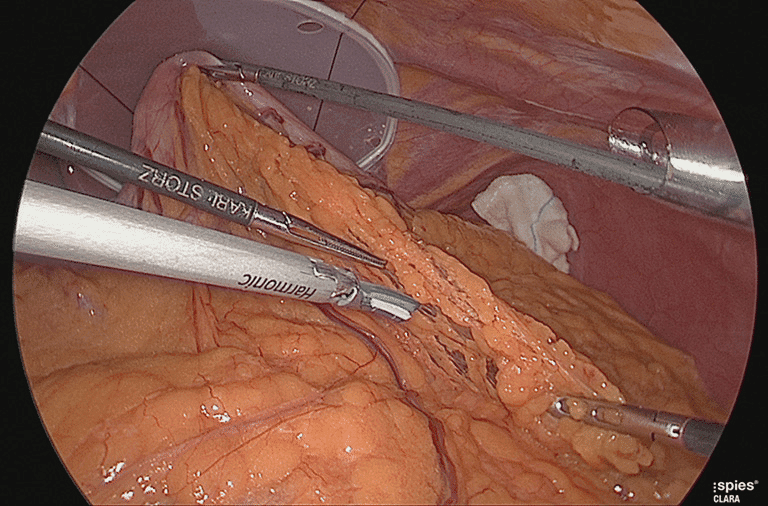

The image below shows you the layers of fat in your belly.

But when you look closely especially on the red arrow.

You’ll see thick layers of skin attached to your belly and almost close to your abdomen.

Now, what most people don’t know is that those layers are considered ‘active’ fat.

Because they more than ever are a part of your body.

Which is why they are hard to lose.

But what makes this layer of skin interesting is that…

They can collapse and also expand.